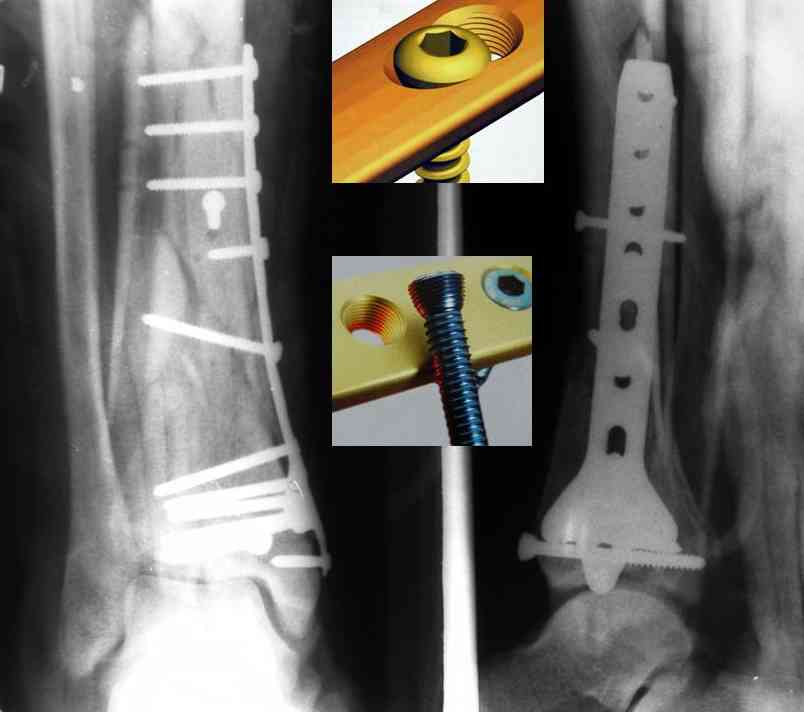

Это типичный перелом пилона, который надп лечить только открыто.Извини те что опоздал к обсуждению, но даже если вы уже оперировали больного по Илизарову это даже лучше.Посылаю картинки.

Посмотрим вроде прошло если понравится напишите расскажу как это сделать.По принципам АО кстати при поступлении сначала восстанавливают длину малоберцовой кости фиксируют пластиной 1/3 трубки потом накладывают аппарат наружной фиксации и через 7-10 дней открыто восстанавливают большеберцовую кость.С уважением Дрягин

На рентгенограммах типичный перелом пилона по типу С-3. есть опыт до 100 открытых опреаций у нас в клинике. 20 примерно в год. Принцип один -все внутрисуставные переломы нуждаются в открытой репозиции и внутренней стабильной фиксации. При поступлении КТ не надо, так как получается только нагромождение костей. Истинной картины нет. Главное восстановить длину малоберцовой кости - это ключ к успеху. При поступлении меньше всего надо думать о сосудистых расстройствах, т.к. сама операция и репозиция даже сначала частичная даёт улучшение сосудитых нарушений. Причём очень быстро. Операция в 2этапа. При поступлении доступ позади наружной лодыжки, причём обязательно. После этого репозиция малоберцовой кости и фиксация пластиной 1/3 трубки под винт 3,5. Дренаж и любой аппарат наружной фиксации. Затем после спадения отёка на 5-7-10 день аппрат снимается и дугообразный разрез спереди от медиальной лодыжки 10-12 см. Главной чтобы расстояние между 1 и вторым разрезом было не меньше 7-8 см. Тогда не будет некрозов лоскутов. Таранная кость используется как матрица на неё укладываются отломки и фиксируются пицами. Ренг-контроль. Отломки лежат все отдельно, но ничего не высыпется. При переломах С-3 всегда нужна костная пластика (из крыла). Фиксация пластиной лист клевера простой или LCP. Гипс не нужен. Дренаж до 48 часов. Операция длится 3-4 часа обязательно без жгута. Посылаю примерно такой же случай.

Кстати, при переломах переднего края по классификации АО В-3 при переломах пилона пластина укладывается по передней поверхности. Она достаточно тонкая и эластичная, не надо этого бояться. Посылаю три снимка.